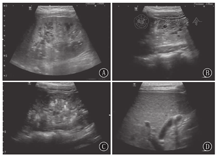

ARPKD是一种儿童最常见的遗传性囊性肾脏疾病[9]。该病存在第6号染色体上的PKDH1基因突变[10],子代个体中1/4发病,而父母双方均无本病表现。肾脏的主要病理学改变为集合管及远端肾小管弥散性扩张,呈放射状排列,从髓质扩展到皮质,部分患者扩张的囊腔内有钙盐沉积或尿酸盐小结晶可见。患儿均出现不同程度的先天性肝脏纤维化。根据发病年龄、肾小管受累数量及肝脏损害程度分为4型:围生期型、新生儿型、婴儿型和少年型。前两型在胎儿或新生儿期就表现为双侧肾脏对称性增大且回声异常,预后较差,通过超声检查可确诊。后两型出生时肝肾病变较轻,无明显临床症状和体征,随着年龄的增长,患儿逐渐出现消化或泌尿系统症状而确诊[11,12]。以往认为肾脏病变程度与肝脏病变程度成反比,年龄越小,肾脏病变越重的患者,肝脏纤维化的程度反而越轻,而有研究认为二者的发展各自独立,并无相关性[13,14]。年龄越小的ARPKD患者肾脏超声影像学特点越典型。胎儿或新生儿患者往往出现双肾对称性明显增大,但并不失去椭圆形的外形,皮髓质分界不清,有时可见外围一圈薄薄的正常肾皮质,严重者肾被膜显示不清晰;低频凸阵探头显示髓质回声增高的典型超声改变,是由于髓质内数量众多的微小囊肿及扩张的小管所产生的声波多重反射形成;线阵高频探头可显示髓质内弥散密集分布的条状或管状微小囊腔结构(扩张的集合管和远端肾小管)或皮髓质散在多发小囊肿,部分患儿囊腔内有钙盐沉积或尿酸盐小结晶形成的成簇成团的点状强回声,为本病的特异性超声表现(图2)。而年龄较大的ARPKD患儿,病变主要以肝胆改变为主、肾脏病变不明显[15],双肾呈轻、中度增大,可能是由于患儿年龄偏大,部分患肾在病程进展中逐渐缩小,因此肾脏增大的患儿较少[9]。有学者使用超声追踪随访ARPKD患者,发现肾脏体积随年龄增大可保持不变,也可逐渐缩小[16]。也有学者认为ARPKD患肾体积的改变与肾功能并无确切相关性[17]。因此,对较大年龄患儿诊断ARPKD,肾脏大小不是诊断的关键,髓质内有无微小囊腔结构及肾实质内有无散在囊肿才是本病主要的诊断依据。怀疑ARPKD的患儿,尤其是对于较大年龄患儿,常规探查肝脏有助于ARPKD的诊断。观察肝内胆管有无扩张,肝叶比例有无改变,肝脏有无纤维化及纤维化的程度等(图2)。一般情况下,肝叶比例改变均表现为左叶增大、右叶缩小[18]。结合临床特点、基因检测结果和超声影像学特点,不难做出ARPKD的诊断。